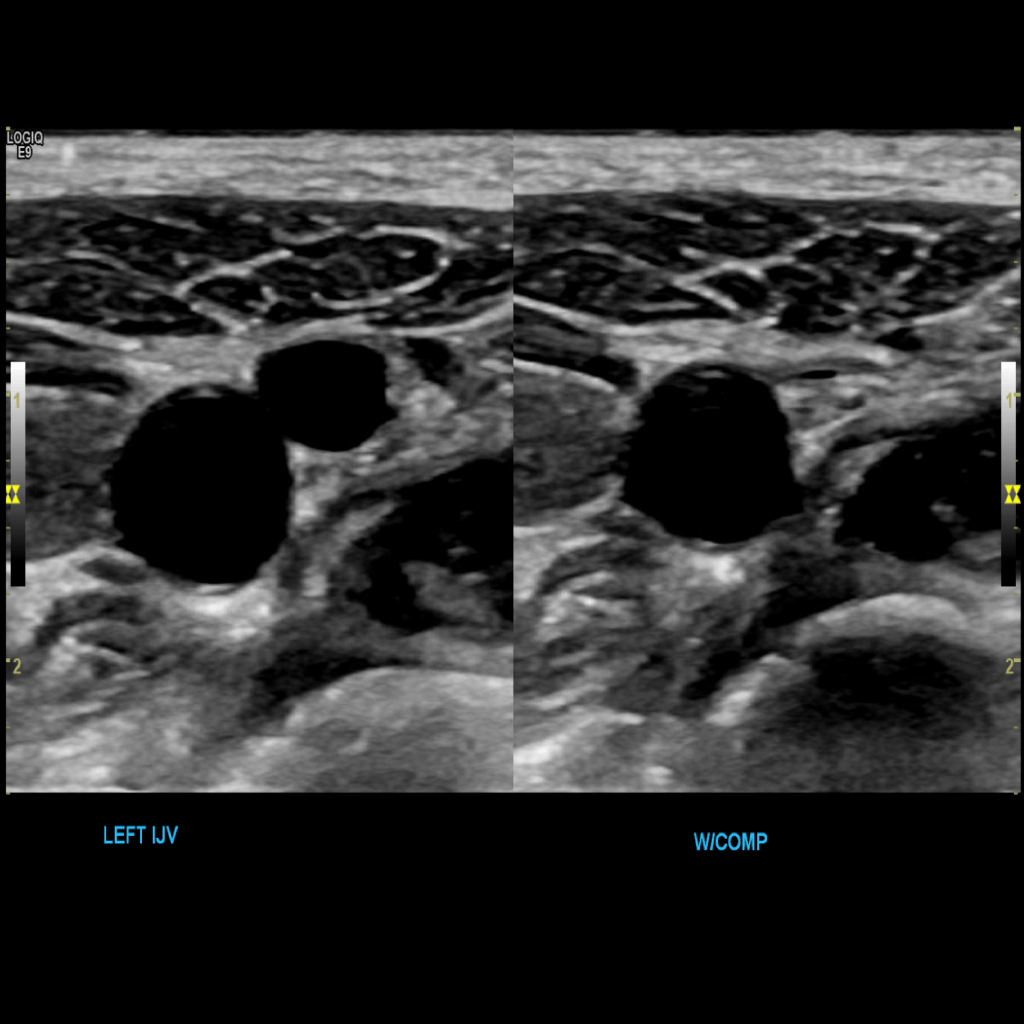

Scan the internal jugular vein in grey scale, compression, color doppler and spectral doppler

A typical scanning protocol includes transverse and sagittal images with and without color doppler and spectral wave analysis of the IJV, subclavian, axillary, brachial, basilic, cephalic, radial and ulnar veins. In my institution we include innominate and superior vena cava (SVC) in the vessels we interrogate.